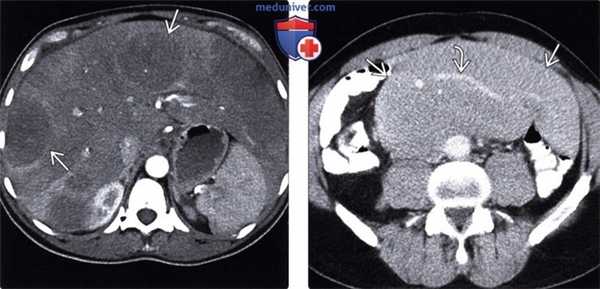

(Слева) При аксиальной КТ с контрастным усилением определяются множественные отдельно лежащие гиподенсные объемные образования в печени, а также выраженная диффузная инфильтрация большей части остальной паренхимы печени, выглядящей гиподенсной. При биопсии был подтвержден лимфоматозный характер инфильтрации.

(Справа) При аксиальной КТ с контрастом определяется большой конгломерат лимфатических узлов в брыжейке. Обратите внимание на сосуды внутри данного конгломерата, которые проходят сквозь него без сужения просвета или окклюзии, что является признаком, характерным для лимфомы.

(Слева) На КТ с контрастным усилением в корональной плоскости у пациента с лимфомой визуализируется выраженное увеличение селезенки, а также множественные мелкие гиподенсные очаги В в ее паренхиме, в связи с диффузным лимфоматозным поражением селезенки.

(Справа) При аксиальной КТ с контрастным усилением определяется большое объемное образование, расположенное в селезенке, распространяющееся кнутри и прорастающее в желудок, который выглядит утолщенным по большой кривизне. Данные изменения являются проявлениями неходжкинской лимфомы (НХЛ). (Слева) При аксиальной КТ с контрастным усилением определяется диффузное увеличение и инфильтрация поджелудочной железы, внешне напоминающие панкреатит.

(Справа) При аксиальной КТ (с контрастом) у этого же пациента определяется распространенная лимфаденопатия брыжейки под поджелудочной железой. Обратите внимание на то, как лимфатический узел располагается вокруг брыжеечных сосудов; такое расположение часто описывается как «симптом сэндвича». Данные изменения, включая увеличение поджелудочной железы, являются проявлениями НХЛ.